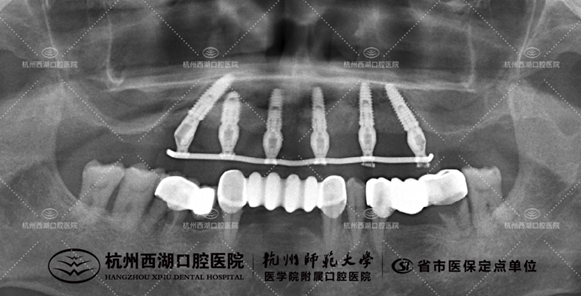

术后CBCT照如下

种植团队采用All-on-6即刻修复技术,为万叔叔上颌植入6颗种植体,即日戴牙完成半口修复。